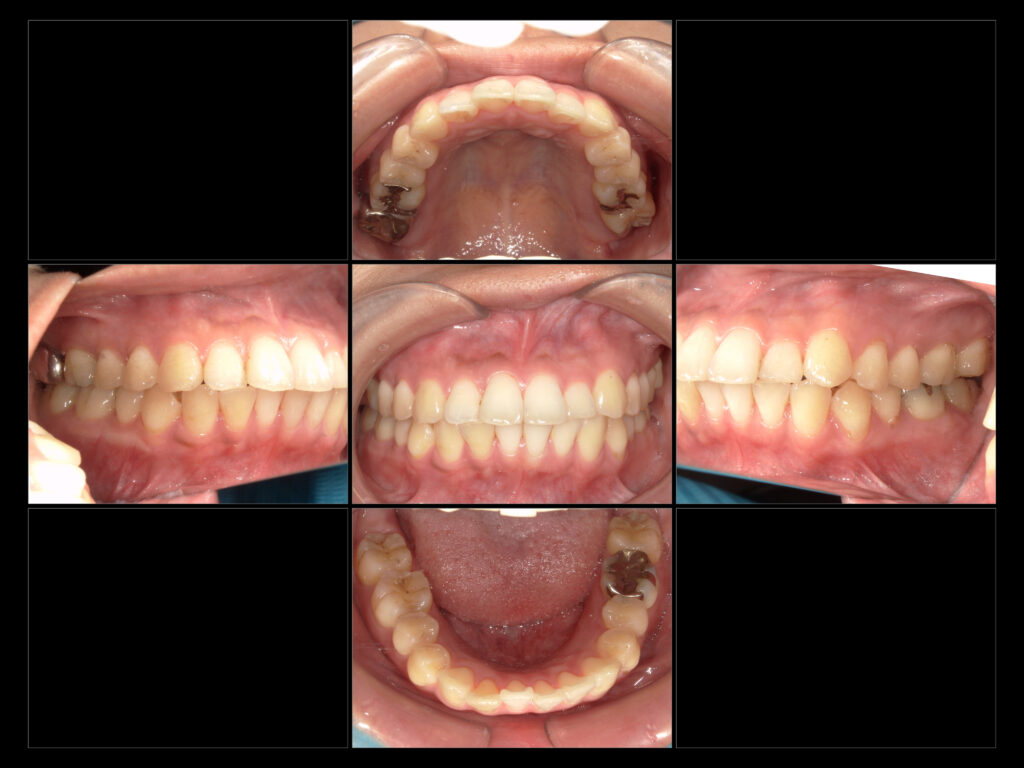

上:初診時口腔内写真

主訴

銀歯の部分をセラミックに変えて予後を良くしたい。

治療内容

e-max In→右上6、右下6、左上6

e-max On →左下6

e-maxCr→右上7

31歳

女性

今回は補綴治療を終えた患者様の症例写真です。